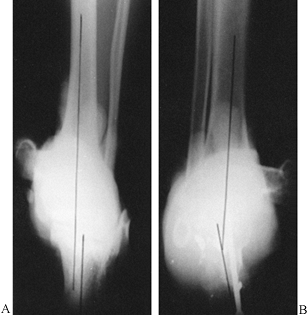

![]() |

Figure 32.12.

When there is subluxation of the knee, the radiographic changes may be subtle. Subluxation of the knee can be defined on the LAT radiograph as a step in the midpoint of the femoral and tibial condyles. Normally, these two points are opposite each other (A). When there is a subluxation of the knee, the midpoint of the tibia will displace anteriorly or posteriorly away from the midpoint of the femur with the knee in extension (B). |

Figure 32.13. A: The knee is dislocated in full extension. B: In 30° of flexion, the knee reduces.

|